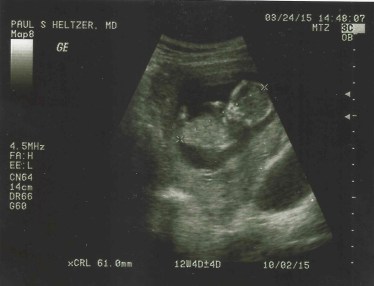

The implantation was scheduled for the first part of January. Then, just days before the procedure, Kristin fell while getting off the ice skating rink at a church youth activity. She tore the mcl and acl in her knee. It seemed as if we just couldn’t catch a break. We felt that we should still move forward with the scheduled IVF implantation even though we didn’t know at that point if Kristin would need surgery for her knee – and thus began days and weeks of waiting. We were elated when we could hear a heartbeat at 6 weeks. But convinced that there wouldn’t be a heartbeat at the next scan a week later. Elated when there was. But sick to our stomaches through the whole next week till the next scan. It was hard to let ourselves have hope that this time it would work.

We were there for about 4 hours. During which, they did finally ascertain that Kristin had an infection that was causing the contractions and that the baby was fine. Kristin is now almost 20 weeks pregnant, and we think we are now ready to start telling people. Mostly, because she can’t hide it anymore. But we are hesitant. We are still scared of a loss.